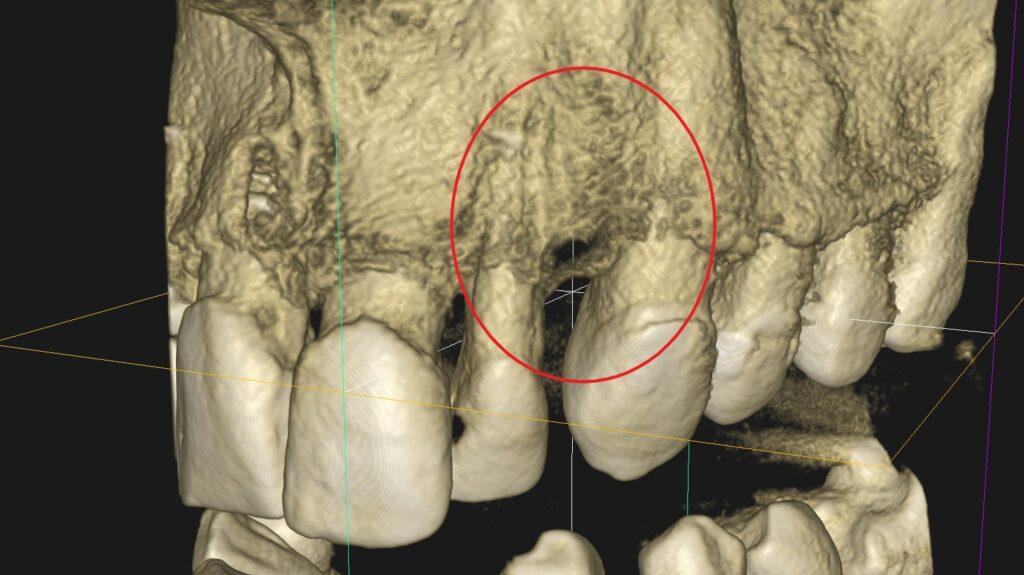

Leczenie kanałowe jest leczeniem skutecznym. Prawidłowe leczenie kanałowe sprawia, że ząb przestaje być ogniskiem zakażenia, a tkanki wokół goją się. Wyleczenie zęba powoduje, że przyczyna choroby tkanek około zębowych [na RTG widzimy jedynie chorobę kości] zostaje usunięta. Eliminacja przyczyny choroby umożliwia gojenie się zmian chorobowych.

Na poniższych zdjęciach RTG – WIDAĆ GOJENIE ZMIAN ZAPALNYCH KOŚCI.

Nie jest prawdą, że leczenie kanałowe w każdym przypadku jest szkodliwe. Ogniskami zakażenia są zęby martwe, nieprzeleczone kanałowo, zęby z nieprawidłowym leczeniem kanałowym i to właśnie one są zagrożeniem i powinny być eliminowane.

W naszej poradni leczenie prowadzą lekarze endodonci, doświadczeni w leczeniu kanałowym, jakość leczenia podnosi stosowanie mikroskopu oraz kontrola radiologiczna. Nasz tomograf umożliwia uwidocznienie kanałów oraz sprawdzenie jakości ich wypełnienia.